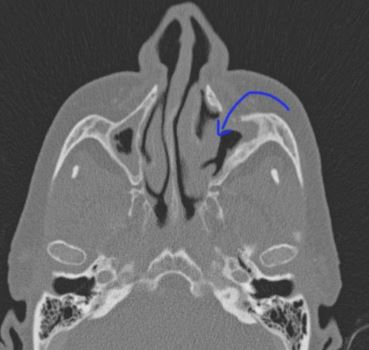

Anatomy of the canine fossa:

The canine fossa is the thinnest portion of the anterior wall of the maxillary sinus. Hence it is

easy to breach this area and enter into the sinus. Boundaries of the canine fossa include:

1. Canine eminence formed by the canine tooth – medial

2. Root of the zygoma – laterally

3. Alveolar process of maxilla - inferiorly

4. Infraorbital foramen with the infraorbital nerve superiorly

Anatomy of canine fossa along with its boundaries

Image showing canine fossa antrostomy

Arrow showing Caldwell Luc surgery opening in the canine fossa